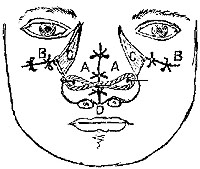

The patient lying down with the shoulders raised and head thrown well back, the sternal attachment of the right sterno-mastoid must be very freely exposed. This may be done by an incision (Plate I. fig. 7) along its anterior edge from the upper edge of the sternum, as far as may be necessary; another about the same length along the upper edge of the clavicle, will meet the former at an acute angle, and will include a triangular flap of skin, which must be carefully dissected up. The sternal, and probably a portion of the clavicular attachment of the right sterno-mastoid, must then be cautiously divided. This being done, the sterno-hyoid and sterno-thyroid muscles require division immediately above their sternal attachments.

A dense process of cervical fascia (just becoming thoracic) now covers the vessel, binding it on the right side to the right innominate vein, and on the left maintaining the relation of the innominate artery to the trachea. The inferior thyroid veins lie on this fascia, and must be drawn aside, not cut. The fascia is then to be scraped through very cautiously, exposing the root of the right carotid, which, being traced downwards, will lead to the innominate. The following parts lie in close relation to the vessel at the point of ligature, and must be avoided:—1. The left innominate vein crosses the artery in front from left to right, and must be drawn down. 2. The right innominate vein and right pneumogastric are in close contact with the artery on the right side; to avoid them the aneurism-needle must be entered on the outside (right of the vessel). 3. The apex of the right pleura and the trachea are in close contact behind, requiring the point of the needle to be kept close to the artery in bringing the thread round.